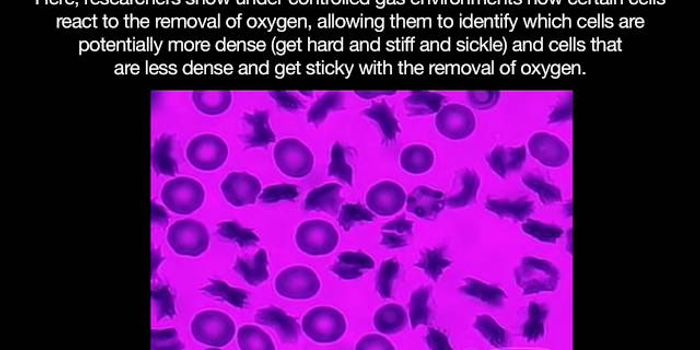

DEC 05, 2018VideosMore than 90,000 Americans and millions of people around the world have SCA.